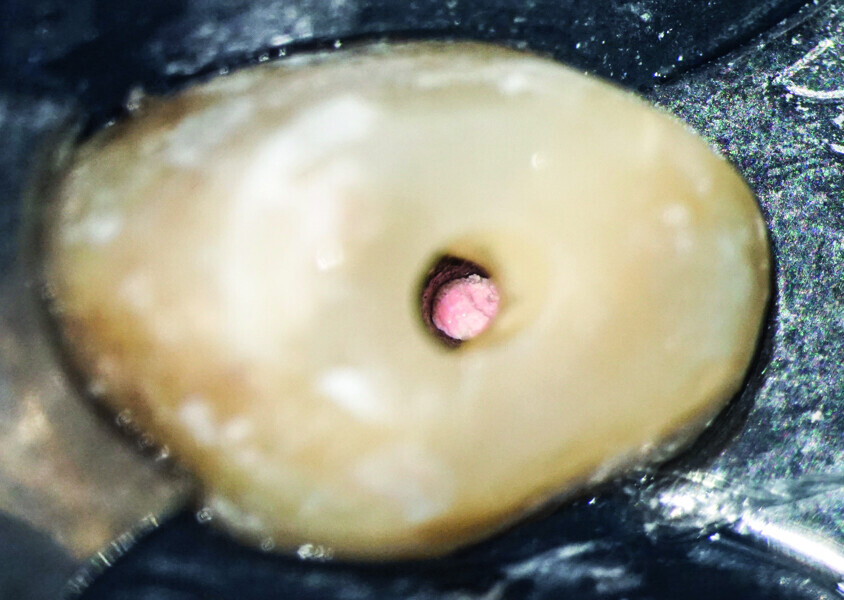

Minimally invasive root canal shaping—A new protocol